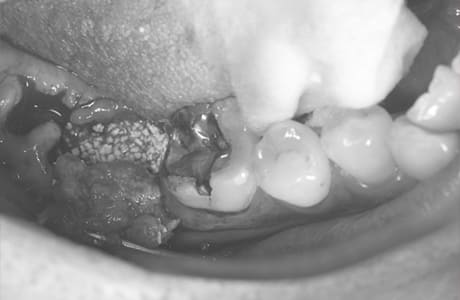

Case12

- 原因

- 左下7番歯牙破折

-

- 治療内容

- インプラント治療

- 治療費用

- 約600,000円

左下の奥歯が痛いとのことでご来院された患者様です。歯が完全に割れており、保存が不可能であったため、抜歯を行い、その際に骨に変わるお薬を入れ、十分な治癒を待ってからインプラント治療を行いました。経過良好で、大変満足されました。

<リスク・副作用>

治療後、痛みや違和感、出血、腫れなどが出る事があります。喫煙者、糖尿病などの方の場合、歯が生着しない場合があります。